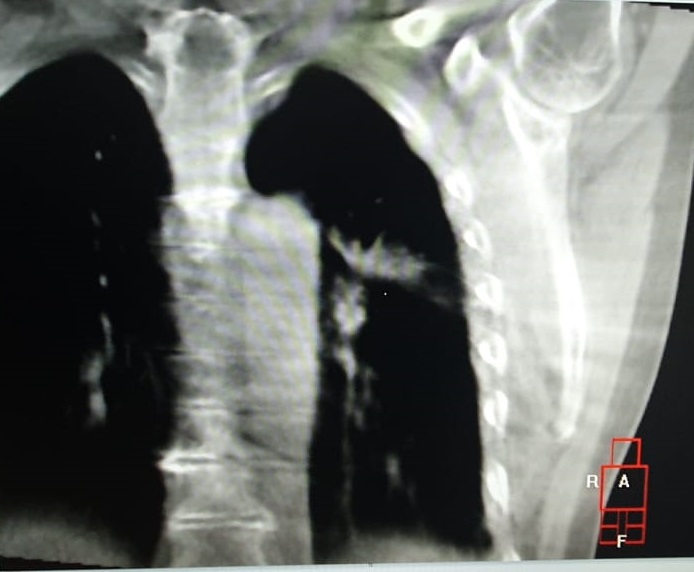

Pacientul M.L. in varsta de 56 ani, fumator de 40 ani, 20PA, s-a prezentat in clinica noastra pe data de 30.11.2022, cu diagnosticul de adenocarcinom pulmonar (neoplasm pulmonar) la nivelul lobului pulmonar superior stang, o tumora in stadiul IIIC, de dimensiuni mari T3, cu invazie ganglionara si mediastinala. Cazul a fost prezentat in Comisia Oncologica Multidisciplinara a clinicii noastre, unde s-a decis initierea tratamentului oncologic. Tumora fiind avansata loco-regional, era exclusa interventia chirurgicala in acest stadiu de boala (cancer pulmonar inoperabil).

Astfel, in perioada 5.12.2022 – 26.01.2023, pacientul a efectuat radioterapie externa cu fotoni, tehnica VMAT-CBCT, pana la doza totala DT = 66 GY/volum tinta formatiune tumorala pulmonara, un numar total de 33 fractii, concomitent cu administrarea saptamanala de polichimioterapie de radiosensibilizare, cu toleranta foarte buna.

Prezentam acest caz la scurt timp dupa finalizarea tratamentului (tratament cancer pulmonar), deoarece acesta este un caz fericit, la care s-a observat un raspuns aproape total chiar din timpul tratamentului RT, imaginile CBCT efectuate la inceputul, in timpul si la finalul tratamentului RT, pe care le atasam, aratand clar un raspuns extraordinar de bun la tratamentul efectuat.